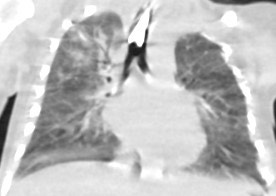

1917. Пациент 3 месяцев с диагнозом «инфантильная фибросаркома мягких тканей шеи слева», после циторедуктивной операции и полихимиотерапии, в стационаре стала нарастать дыхательная недостаточность, выполнена компьютерная томография, рентгенологическая картина соответствует